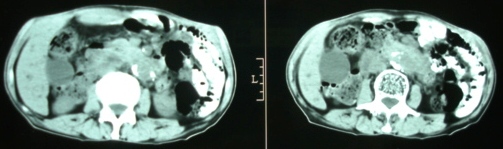

m/72y,皮肤巩膜黄染6个月。

ct意见:1、胆总管结石并肝内胆管、胰管扩张。

2、胆囊结石并胆囊炎。

胆道系统结石并胆系扩张。